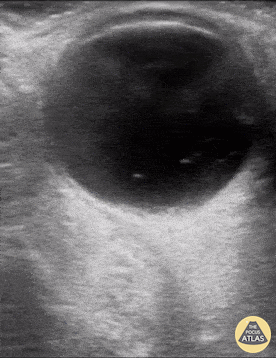

Orbital - Vitreous Hemorrhage

An 81 yo female on ASA presented with 6 hour hx of blurred vision in her right eye. Ocular POCUS demonstrated a hyperechoic clot, seen here as 'swirling' movement, with debris settling near the bottom of the globe when eye is not in motion (end of clip). In early presentation of vitreous hemorrhage when blood is still liquified, increasing the ultrasound gain can greatly assist with identification of pathology. Mandy Peach, MD @mandy_peach Saint John Regional Hospital. NB, Canada